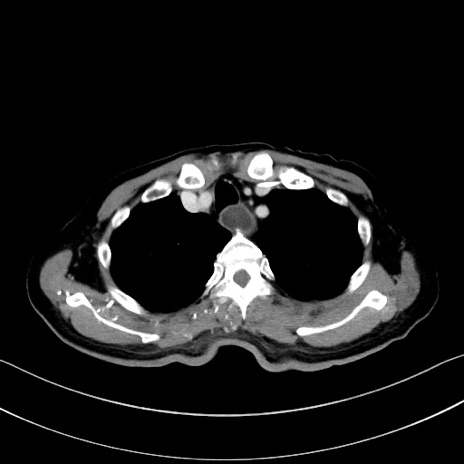

症例28(横断像)

【症例】60歳代男性

【主訴】嘔吐

【現病歴】胃癌にて胃全摘後。食思不振が悪化し、夜中に嘔吐することがある。

【既往歴】胃癌、胃全摘、脾摘、胆摘後

【データ】WBC 5900、CRP 10.56